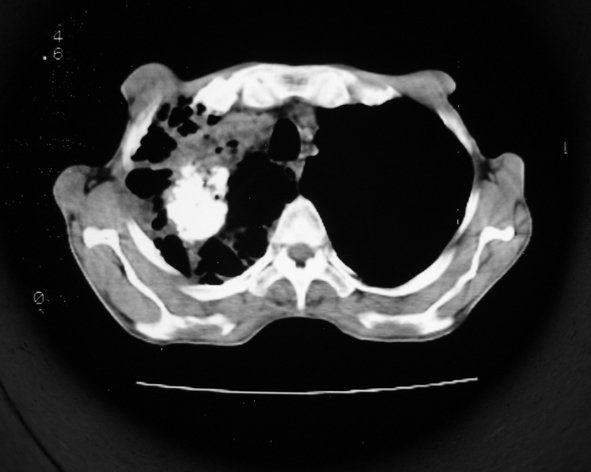

男53岁,咳嗽气短,以往身体健康.

右肺上叶多发多形态空洞及增殖灶,可见团块钙化,胸膜肥厚、粘连,考虑继发型肺结核可能性大

1.右肺上叶干酪性肺炎,2。肺气肿,肺大泡

支持:继发型肺结核合并干酪性肺炎

支持右上肺继发性肺结核并干酪性肺炎,右肺大泡,左肺代偿性气肿。